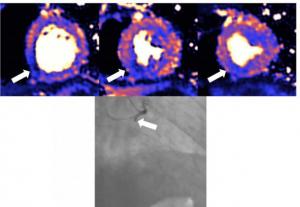

Around 50% of patients who have been hospitalised with severe COVID-19 and have raised levels of troponin have heart damage, according to a study published in the European Heart Journal. The injury was detected by magnetic resonance imaging (MRI) scans at least a month after discharge and includes myocarditis, infarction, ischaemia and combinations of all three.